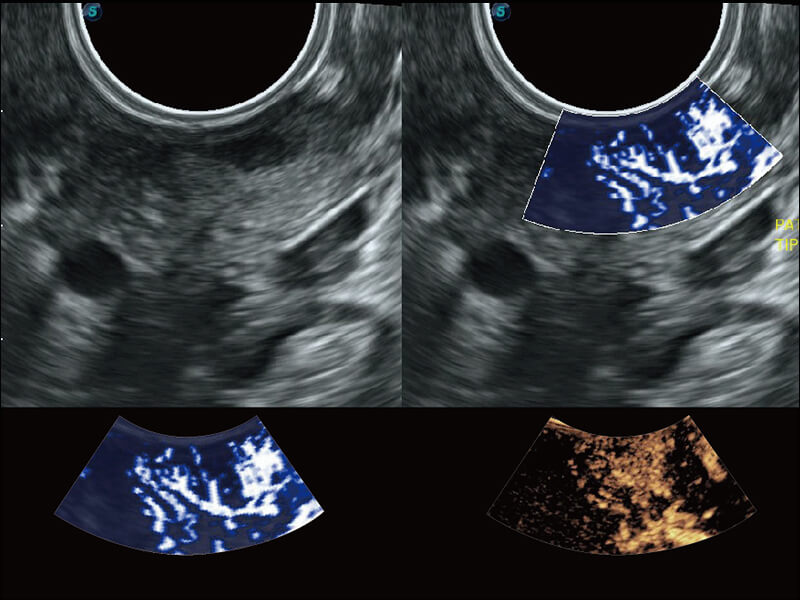

成像功能

S60探头工艺,从前端信号处理每一个环节采集无损声学数据,真实还原组织原貌,再现解剖细节。